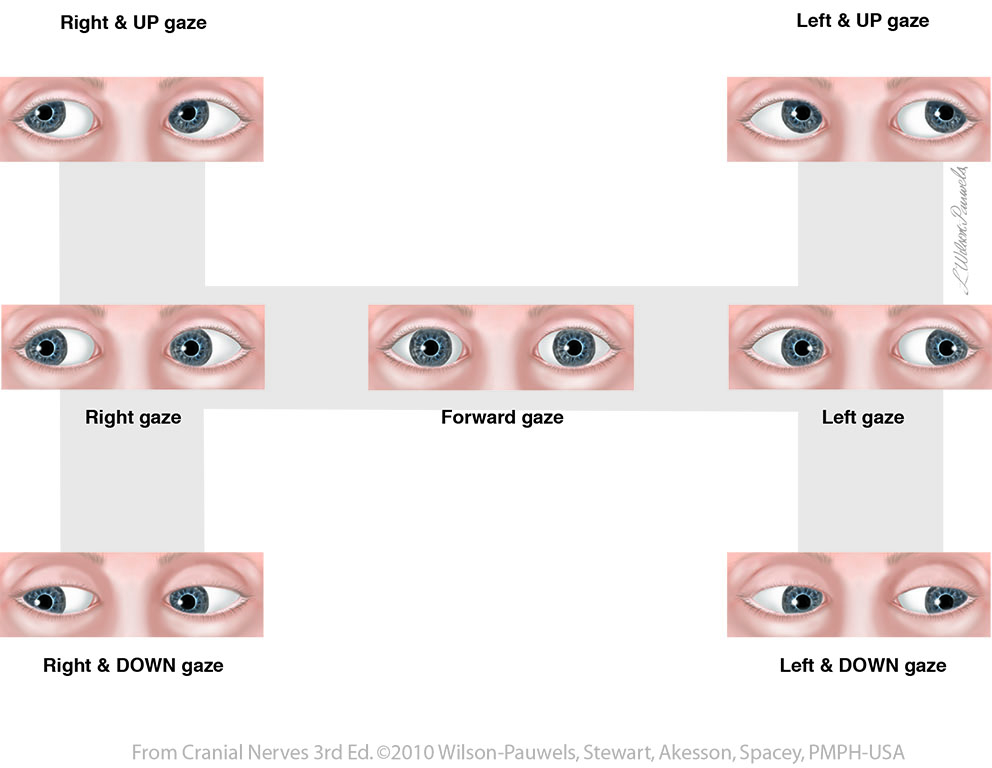

Cranial Nerves 3rd Edition: Eye Movements

bmc.utm.utoronto.ca

bmc.utm.utoronto.ca

movements oblique inferior rectus cranial nerves medial

Cranial Nerves 3rd Edition: Eye Movements

bmc.utm.utoronto.ca

bmc.utm.utoronto.ca

cranial nerves rectus lateral medial movements